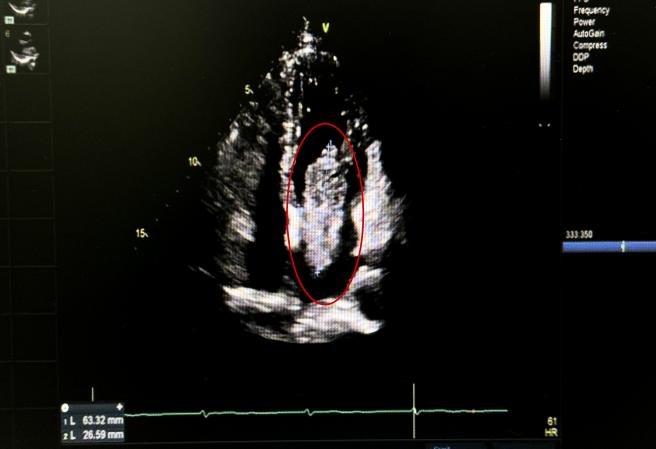

患者因一周前无明显诱因下出现活动后胸前区闷痛,向背部肩胛区放射来院就诊。经检查发现,患者心脏肿瘤压迫心脏及周围血管,导致呼吸困难。经过与患者的沟通,心脏大血管外科团队决定为患者行单孔胸腔镜下心脏肿瘤切除术。